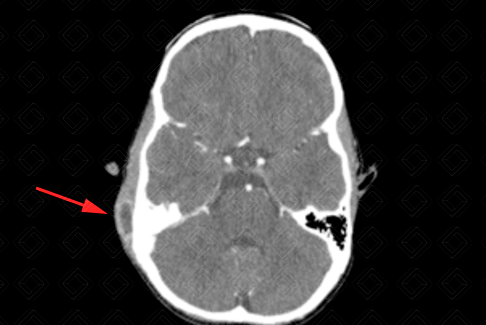

Descrição das figuras: Tomografia computadorizada das mastoides com contraste venoso. Observa-se no plano axial com filtro ósseo o preenchimento das células mastoideas à direita. As células mastoideas à esquerda encontram-se normoaeradas. Há ainda presença de coleção no ouvido externo à direita (setas vermelhas). Os planos axial e coronal caracterizam um quadro de otomastoidite à direita.

Mastoidite aguda: Trata-se da infecção das células mastoideas, representando a complicação mais comum das otites. Deve ser realizada com contraste venoso, para afastar possíveis complicações como coleções, trombose de seios venosos, erosões ósseas, osteomielites de base do crânio, abscessos cerebrais, meningite e outras

• Tomografia computadorizada das mastoides: O bserva-se preenchimento das células mastoides, com erosão dos septos. Deve ser realizada após a administração do contraste venoso para afastar complicações, como coleções, trombose de seios durais, abscessos cerebrais, osteomielite, erosões ósseas e outros;